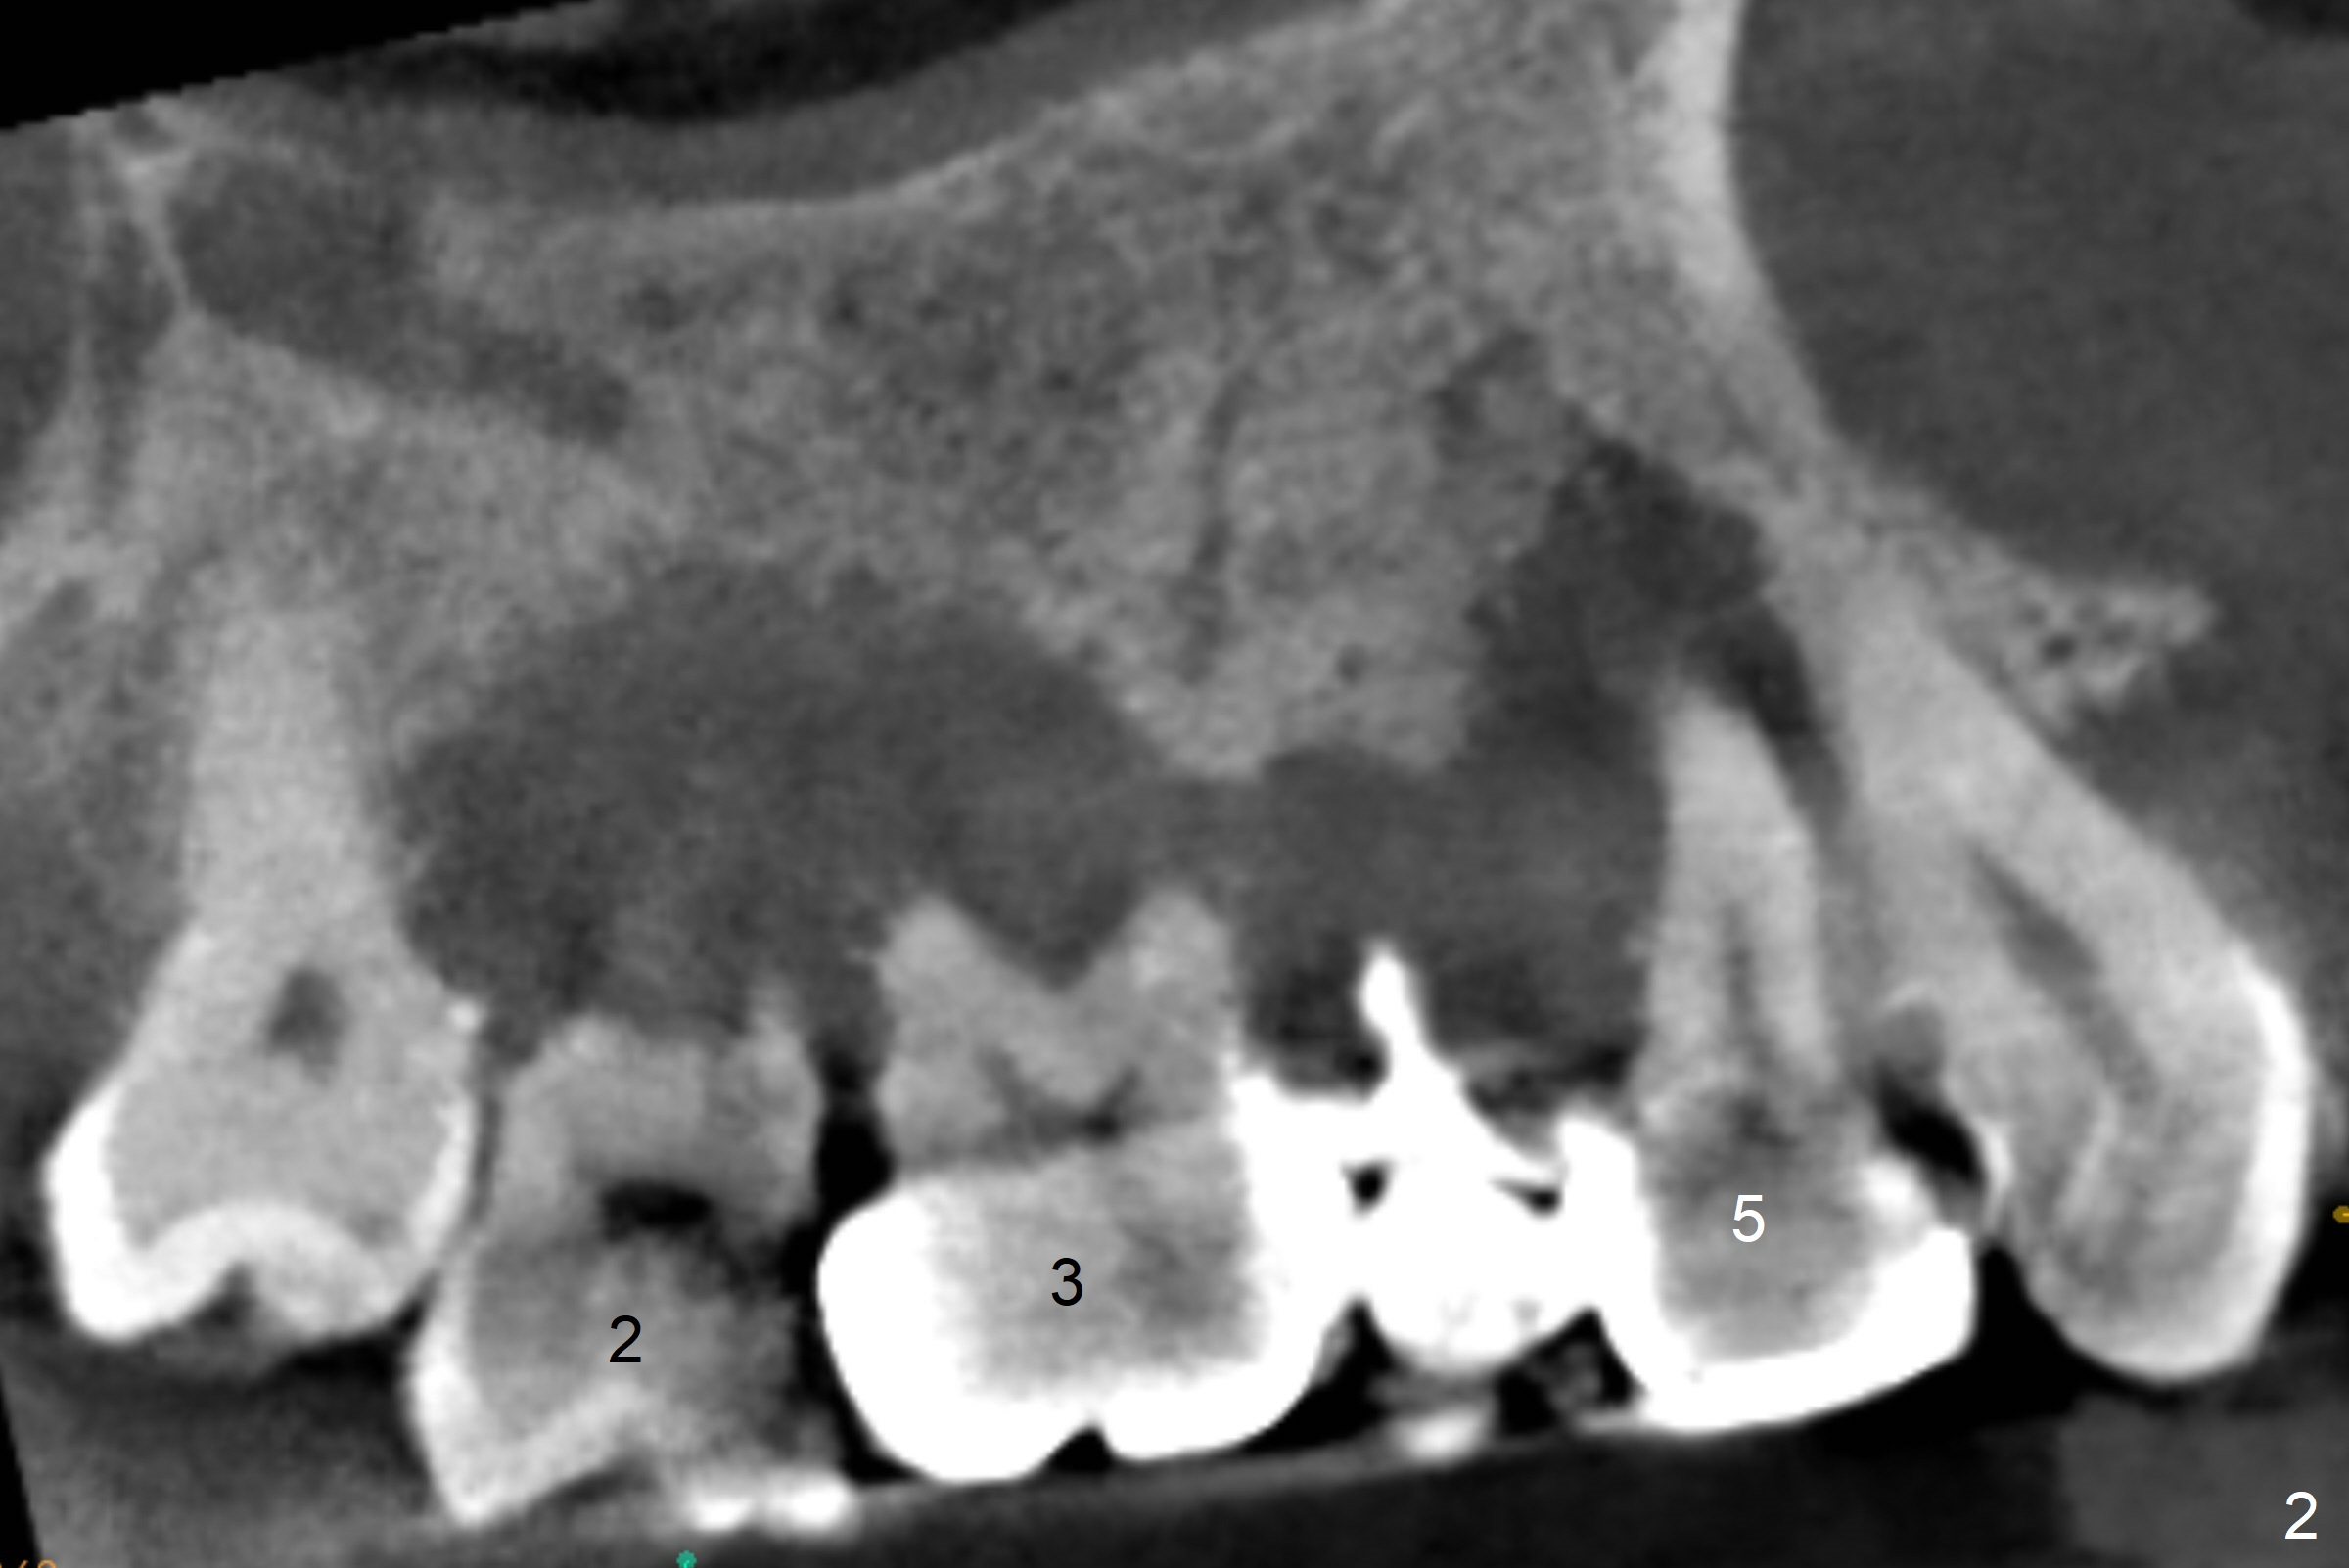

A 45-year-old man will return for #2, 3 and 5 extraction and implants (Fig.1,2). Take PAs for and Reline #7,9,11 provisional crowns and fabricate #11-13 temporary FPD if #15 implant is still unstable (5 months postop). Establish normal occlusal contact.

Extract #2 or remove #3-5 FPD first whichever is looser. Use the other as reference guide. Place Osteogen plug in the palatal socket of #2 ad 3 (Fig.3,4 yellow box) and allograft around the implants (red circles).